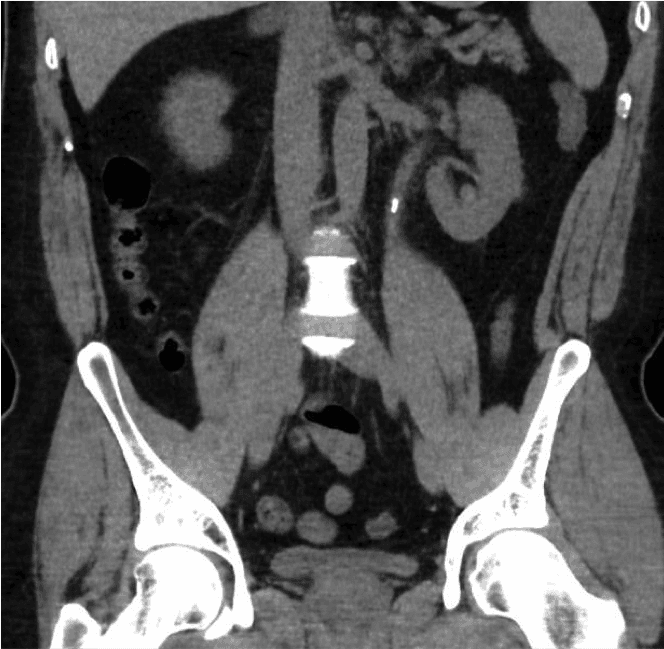

La lithiase rénale est l'une des maladies les plus courantes de l'ère moderne. Sa prévalence varie considérablement selon les zones géographiques, allant de 8 % à 19 % chez les hommes et de 3 % à 5 % chez les femmes dans les pays occidentaux [1,2]. Au Royaume-Uni, le nombre d'hospitalisations dues à des calculs rénaux a augmenté de 63 % entre 2000 et 2010, pour atteindre 83 050 [3]. La prévalence croissante de la lithiase représente un fardeau économique et clinique majeur pour notre système de santé.Les calculs rénaux peuvent apparaître fortuitement lors d’un examen réalisé pour d’autres raisons ou présenter des symptômes tels que des douleurs, une infection urinaire ou une hématurie (sang dans les urines).